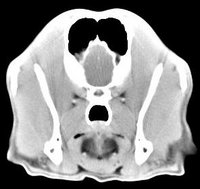

imágenes de TC en el perro | ||||||||||

ejemplo de imágenes de TC en el perro. Nótese la celulitis en la región parotídea izquierda | ||||||||||